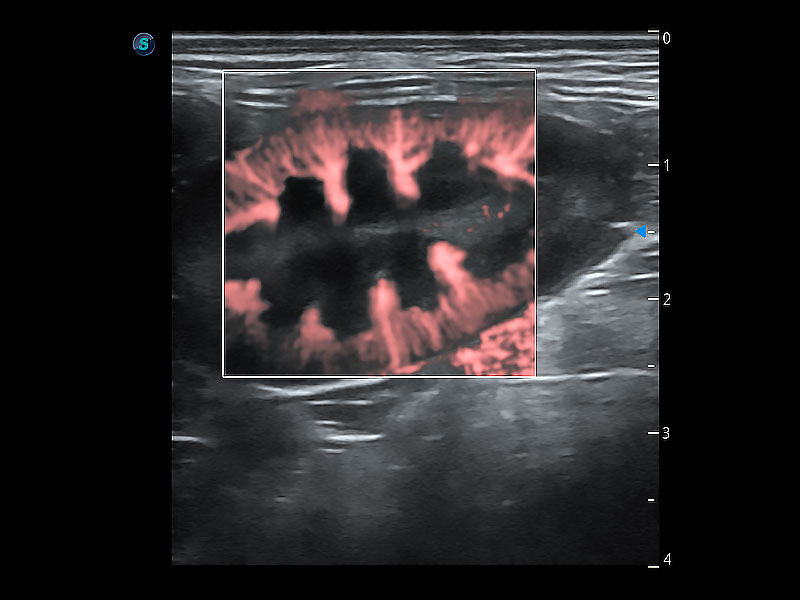

极大提升超低速微细血流的检出能力,同时更精准地滤除软组织和超声信号,为兽用医生提供以往无法通过常规血流获得的疾病诊断信息。

在传统二维血流成像的基础上,呈现血流的立体感,具有动感的生命力之美。即便是微小的血管也能轻松应对,提高了血流的视觉敏感性。